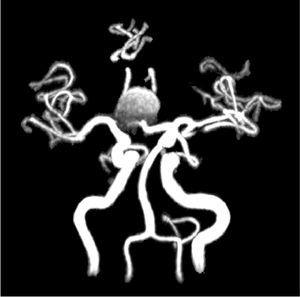

Se realiza una angio-RMN (resonancia magnética nuclear), sin contraste por su insuficiencia renal avanzada, y en ella se observa la presencia de un aneurisma sacular gigante de 19 x 16 mm en la arteria comunicante anterior (figura 1 y figura 2). Se decide tratamiento conservador, dado que los segmentos distales de las arterias cerebrales anteriores (ACA) salen del propio aneurisma y, si se emboliza o se clipa, se produciría isquemia de los territorios irrigados por las ACA.

Figura 1. Angio-resonancia magnética nuclear 3D.